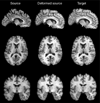

Methods: 3D T1-weighted brain MRIs of 26 AIDS patients (CDC stage C and/or 3 without HIV-associated dementia; 47.2+/-9.8 years; 25M/1F; CD4+ T-cell count: 299.5+/-175.7/microl; log10 plasma viral load: 2.57+/- 1.28 RNA copies/ml) and 14 HIV-seronegative controls (37.6+/-12.2 years; 8M/6F) were fluidly registered by applying forces throughout each deforming image to maximize the JRD between it and a target image (from a control subject). The 3D fluid registration was regularized using the linearized Cauchy-Navier operator. Fine-scale volumetric differences between diagnostic groups were mapped. Regions were identified where brain atrophy correlated with clinical measures.

Results: Severe atrophy ( approximately 15-20% deficit) was detected bilaterally in the primary and association sensorimotor areas. Atrophy of these regions, particularly in the white matter, correlated with cognitive impairment (P = 0.033) and CD4+ T-lymphocyte depletion (P = 0.005).